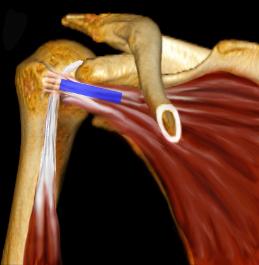

Long axis of the Bicep

over the Anterior

Humeral Head, just

lateral to the Coracoid

Process.  Saggital

oblique Body plane as

the Biceps makes its

way to the superior

Labrum.